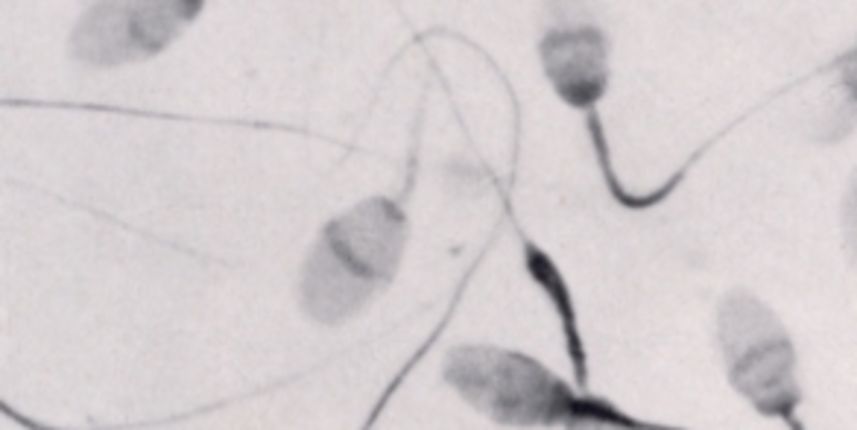

Britanski znanstvenici stvorili su umjetnu ljudsku spremu uz pomoć matičnih stanica. Ovo otkriće moglo bi donijeti revolucionarne pomake u liječenju neplodnosti. Znanstvenici su se koristili stanicama uzetim iz embrija, a tvrde da će nakon manjih promjena sperma biti kvalitetna te da će moći oploditi jajašce i stvoriti dijete.

‘Ovo je nevjerojatno otkriće. Stvorili smo prave spermije – imaju glave, repove i kreću se. Oblik i kretanje nisu baš kao kod pravih spermija, ali sadržavaju proteine koji su nužni za oplodnju jajašaca’, pojasnio je profesor Karim Nayernia, biolog koji je vodio istraživanje.